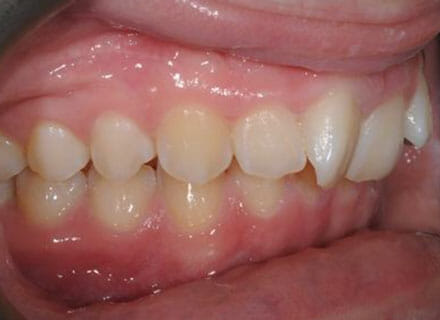

In this case, the upper incisors had a pushed back appearance and they were twisted. the smile was narrow – when the patient smiled the sides of the smile were in shadow. we used clear brackets to gently untwist and straighten the front teeth while widening the upper arch/jaw to broaden the smile. this patient was beaming for the first time in just 12 months.